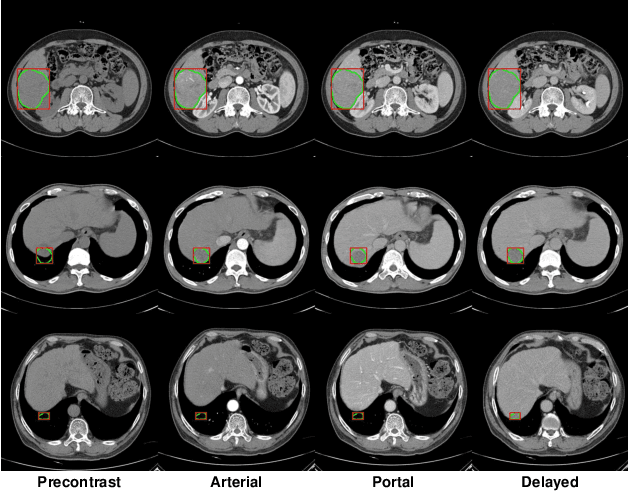

Abstract:The computer-aided diagnosis of focal liver lesions (FLLs) can help improve workflow and enable correct diagnoses; FLL detection is the first step in such a computer-aided diagnosis. Despite the recent success of deep-learning-based approaches in detecting FLLs, current methods are not sufficiently robust for assessing misaligned multiphase data. By introducing an attention-guided multiphase alignment in feature space, this study presents a fully automated, end-to-end learning framework for detecting FLLs from multiphase computed tomography (CT) images. Our method is robust to misaligned multiphase images owing to its complete learning-based approach, which reduces the sensitivity of the model's performance to the quality of registration and enables a standalone deployment of the model in clinical practice. Evaluation on a large-scale dataset with 280 patients confirmed that our method outperformed previous state-of-the-art methods and significantly reduced the performance degradation for detecting FLLs using misaligned multiphase CT images. The robustness of the proposed method can enhance the clinical adoption of the deep-learning-based computer-aided detection system.

Abstract:We present a focal liver lesion detection model leveraged by custom-designed multi-phase computed tomography (CT) volumes, which reflects real-world clinical lesion detection practice using a Single Shot MultiBox Detector (SSD). We show that grouped convolutions effectively harness richer information of the multi-phase data for the object detection model, while a naive application of SSD suffers from a generalization gap. We trained and evaluated the modified SSD model and recently proposed variants with our CT dataset of 64 subjects by five-fold cross validation. Our model achieved a 53.3% average precision score and ran in under three seconds per volume, outperforming the original model and state-of-the-art variants. Results show that the one-stage object detection model is a practical solution, which runs in near real-time and can learn an unbiased feature representation from a large-volume real-world detection dataset, which requires less tedious and time consuming construction of the weak phase-level bounding box labels.